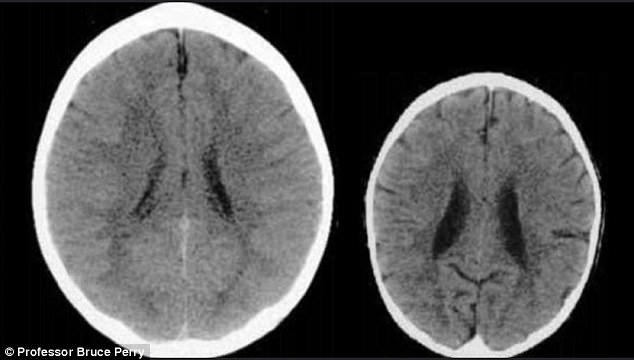

For a visual look of what this does, the picture below is from a study by Professor Bruce Perry showing the brain of a normal, healthy five year old on the left, and an extremely neglected child, such as Mac-Mac, on the right. It’s important to emphasise that these pictures are of two children of the same age.